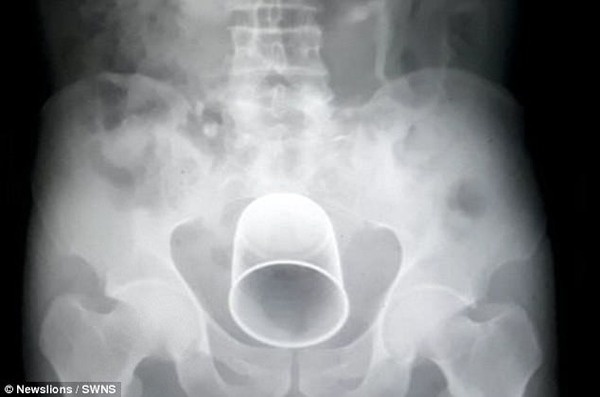

ー体内から21センチの金属コップ

今回話題となっているのは、インドのとある農村で治療を行った60代の男性です。どうやらその男性は、村の医者に何らかの治療を行ってもらったのですが、その治療後、あまりの激痛に悶絶し、今回の私立の医者に来院。そこでレントゲン等を撮って驚きの事実が発覚したのです。なんと体内から21センチの金属コップが出てきたのです。

1時間半の手術の末、無事金属コップは取り出されましたが、一体どういう意図があったのか謎です。また患者もこのコップが入れられていたことに相当驚いたそうです。